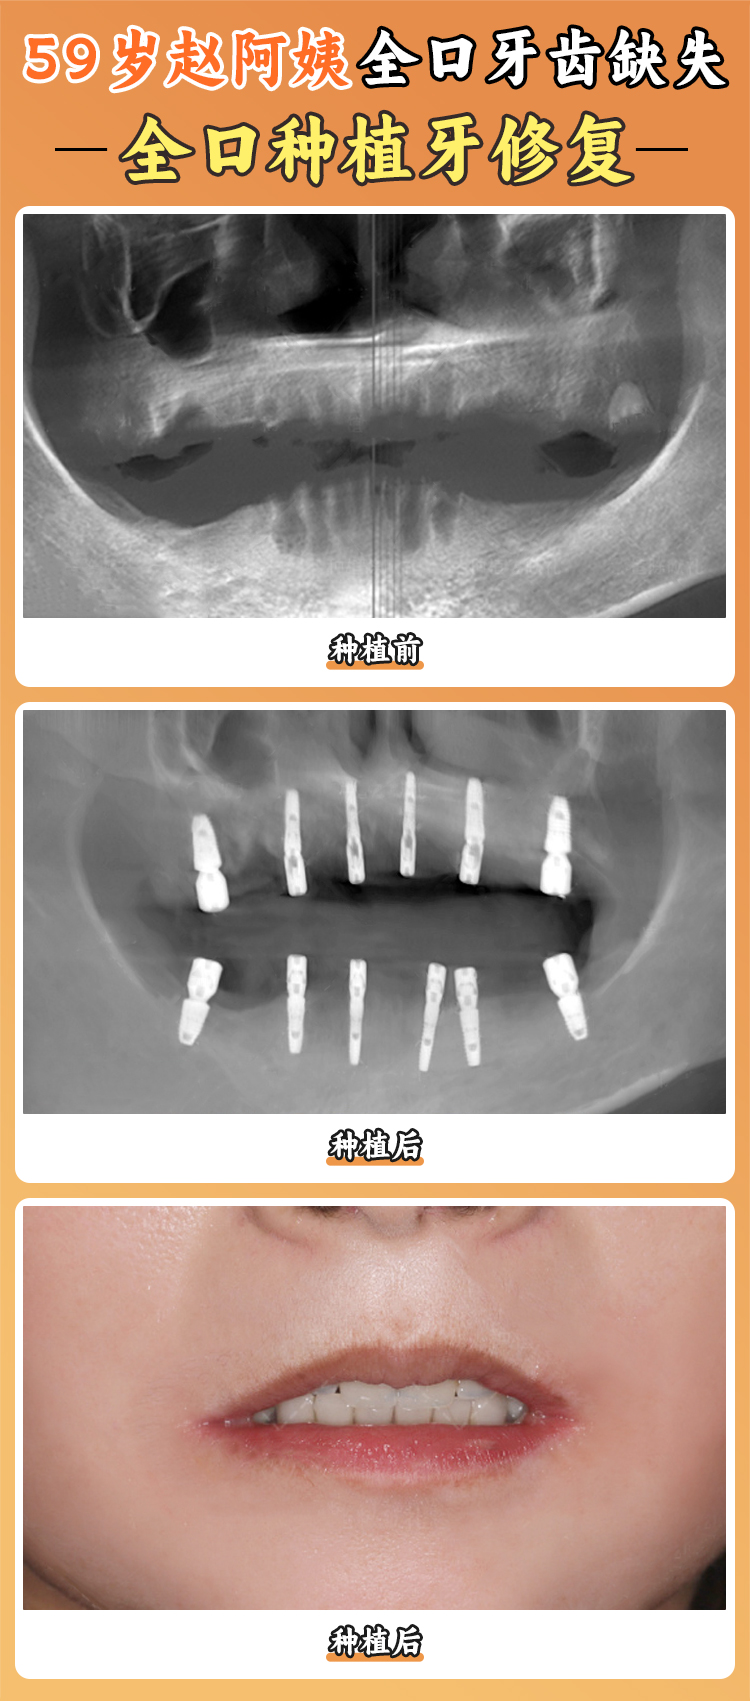

半口和全口种植牙价格:对于半口牙齿缺失的患者,贝臣口腔医院提供了从9999元起的半口种植牙项目,能带来更舒适和美观的牙齿修复成效。全口牙齿缺失的患者也不用担心,贝臣口腔医院的全口种植牙项目从19800元起。